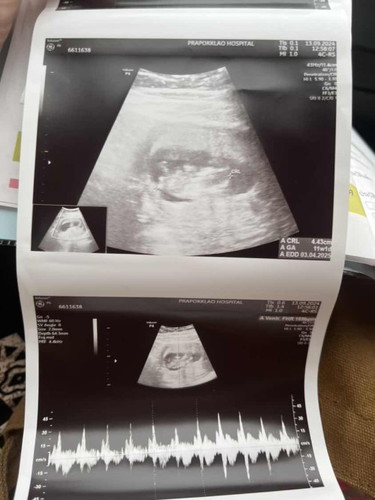

แฝด 👶🏻👶🏻 พอดีหนูอยากจะรู้ ว่าขนาดของเจ้าแฝดน้อยเนี่ย ตามเกณฑ์ไหมค่ะ คนนึง 4.49cm อีกคน 4.43cm

ตามเกณฑ์ค่ะเเม่😊